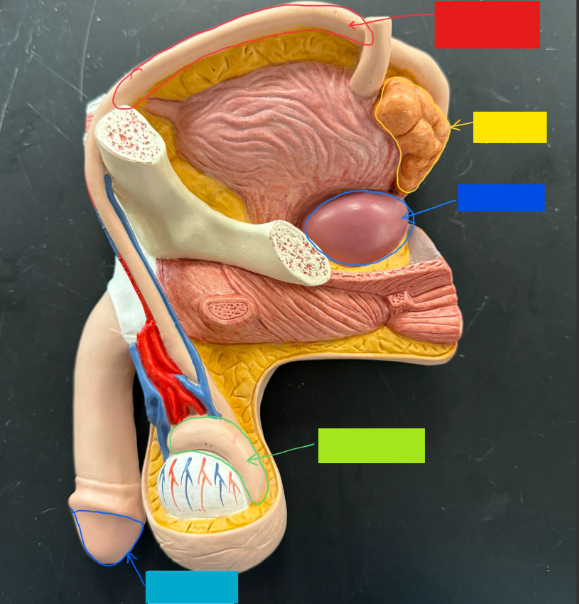

What is the name of the red box?

Vas deferens

What is the name of the yellow box?

Seminal vesicle

What is the name of the blue box?

Prostate

What is the name of the light green box?

Epididymis

What is the name of the light blue box?

Prepuce